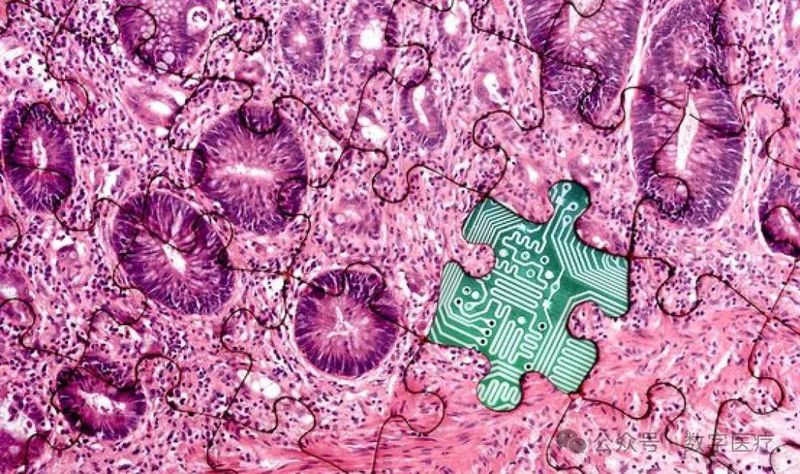

生成式人工智能(AI)近年来在多个领域展现出巨大的潜力,尤其是在医学领域。解剖病理学作为医学诊断的重要组成部分,依赖于对组织和细胞的显微镜检查,生成式AI的应用有望显著提升诊断准确性、工作流程效率以及科研和教育能力。本文综述了生成式AI在解剖病理学中的应用、优势、挑战以及未来的潜力。

一、生成式AI在解剖病理学中的应用

1、图像分析

虚拟染色:生成式AI可以通过计算算法将现有的组织切片图像转换为具有特定染色的图像,从而减少病理学家的工作负担。例如,GANs已经成功应用于将冷冻切片图像转换为福尔马林固定、石蜡包埋的组织图像,以及在不同染色之间进行转换。

合成图像生成:生成式AI可以生成合成组织学图像,用于增强数据集的多样性,特别是在癌症预测任务中,合成图像可以防止模型过拟合,提高泛化能力。